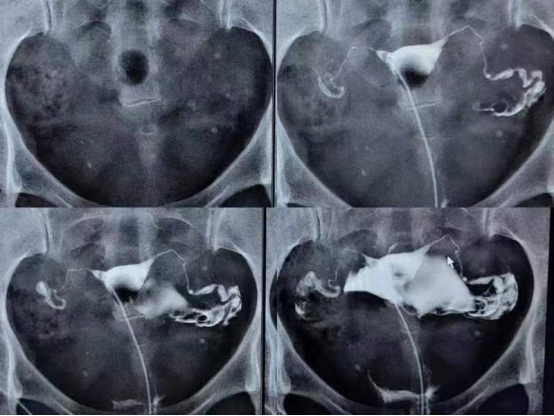

科室主要仪器设备:锐柯双板DR机、西门子胃肠造影机、法国双能X线骨密度仪、高端移动DR机两台。科室现已开展头颅、胸腹部、四肢及脊柱等部位常规检查;消化、泌尿、子宫输卵管及“T”管造影;双下肢及脊柱全长影像技术;骨密度检查(成人及儿童)和为危重病人服务的床旁摄片业务。